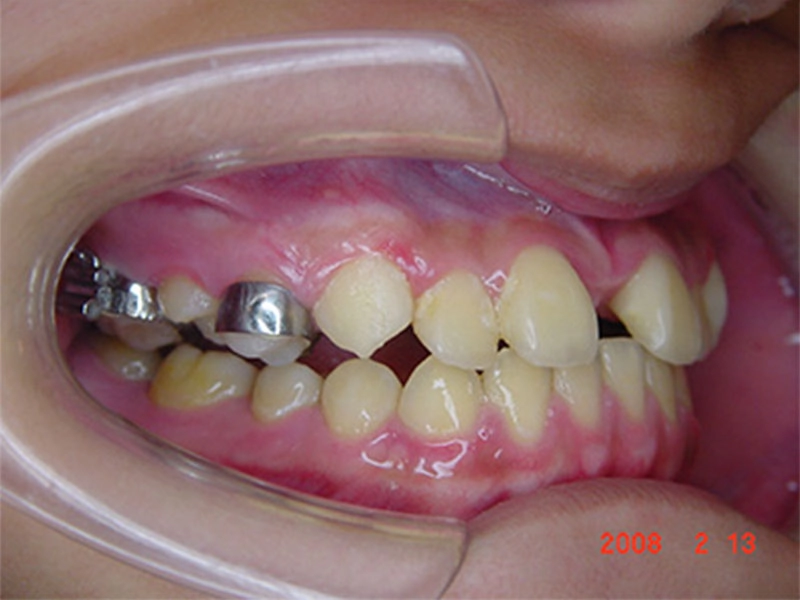

矯正 21 天後 上顎骨及鼻樑向前突出 戽斗改善

戽斗矯正案例-4